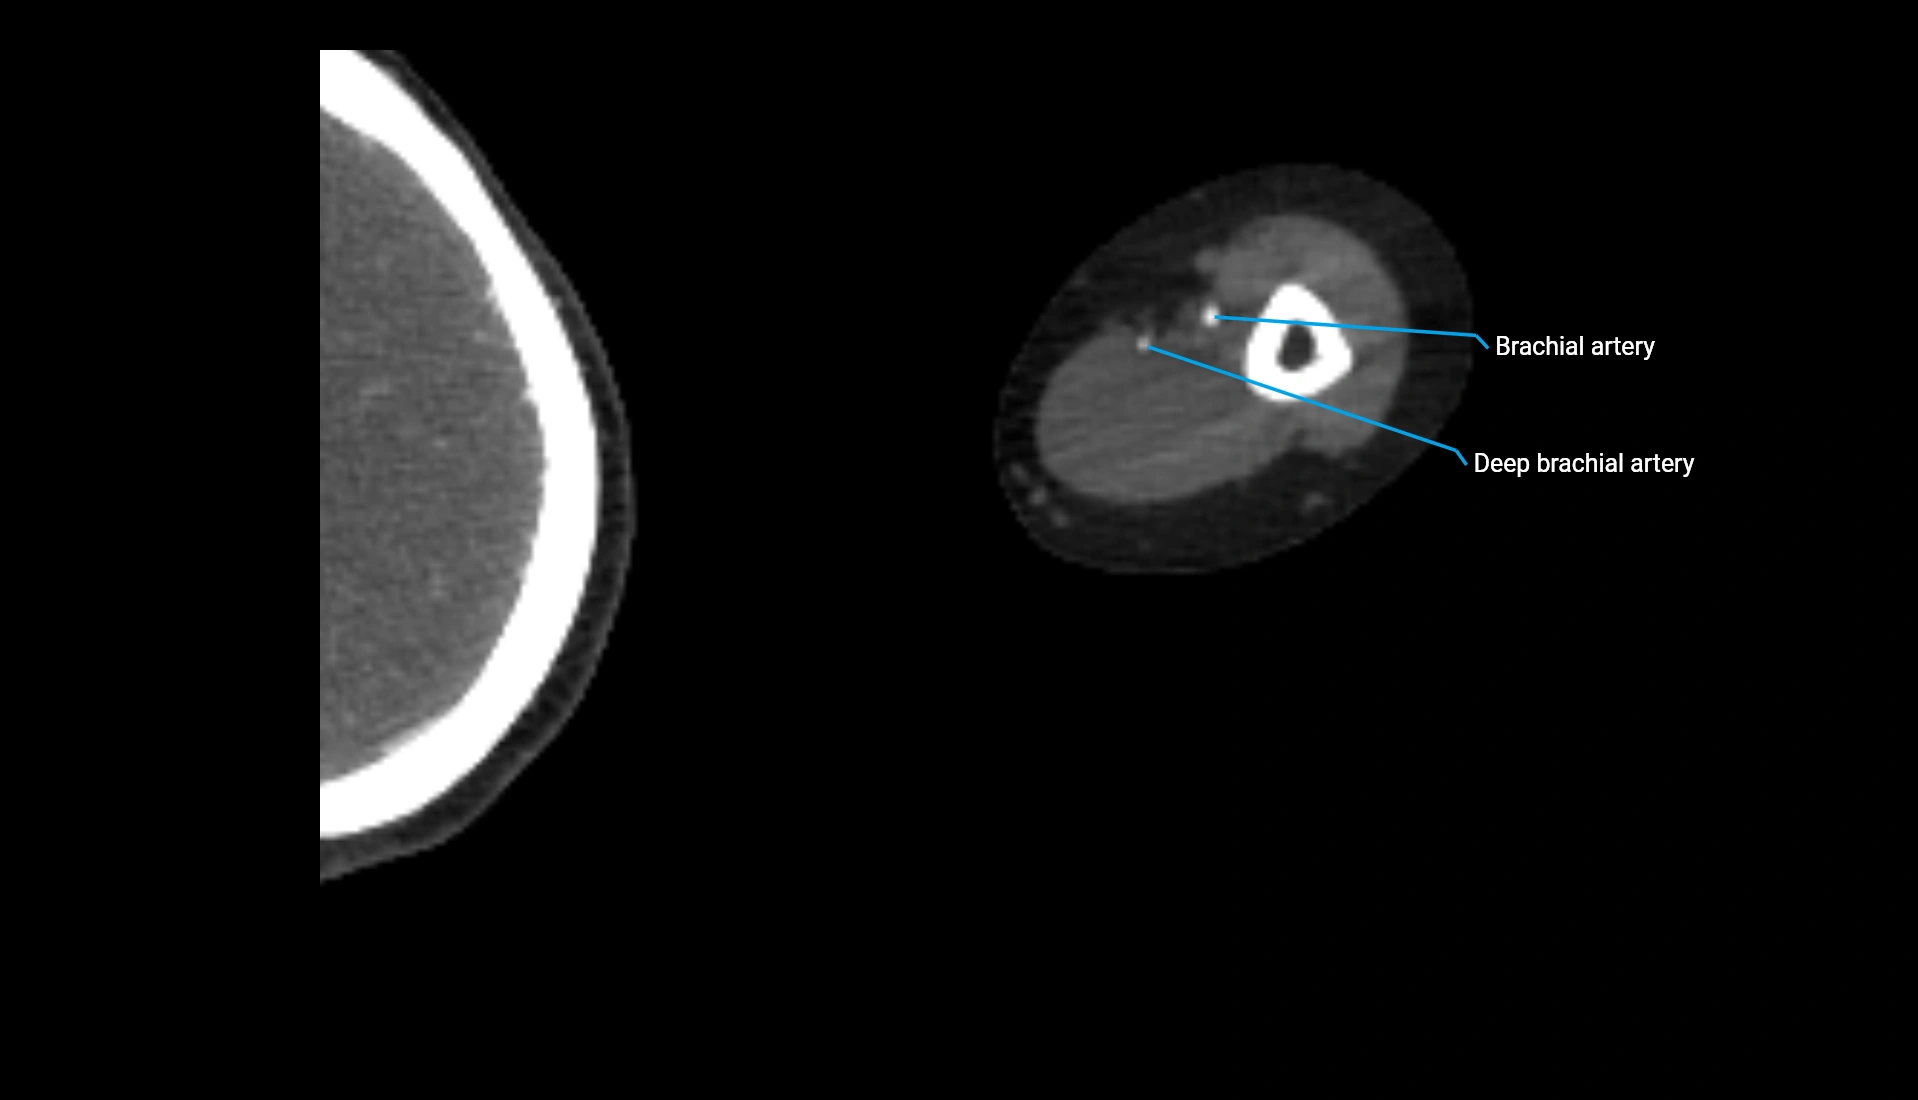

CT Appearance

Non-Contrast CT:

• Cortex: High-density, sharply defined

• Subchondral bone: Dense cancellous matrix

• Articular surface: Smooth concave contour articulating with the capitellum

• Excellent for evaluating bone integrity, alignment, and subtle fractures

Post-Contrast CT:

• Bone: No enhancement

• Joint capsule and synovium: Mild enhancement outlining the joint

• Improves contrast between soft tissues and bony margins

• Useful in detecting subtle joint abnormalities or postoperative changes